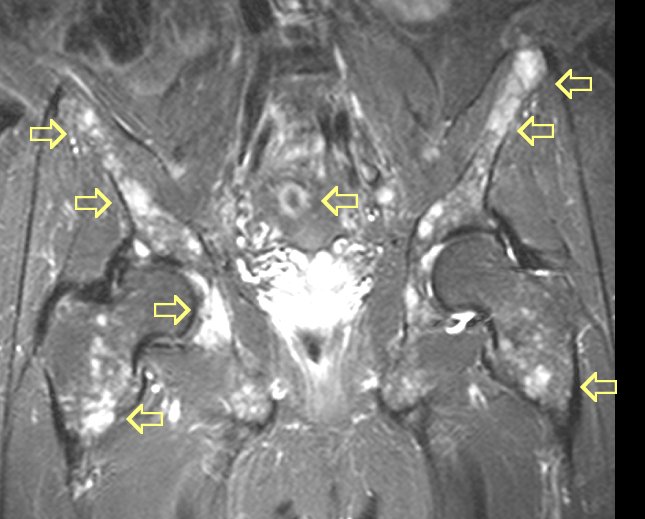

#7 MRI images of very diffuse disease

here and

here